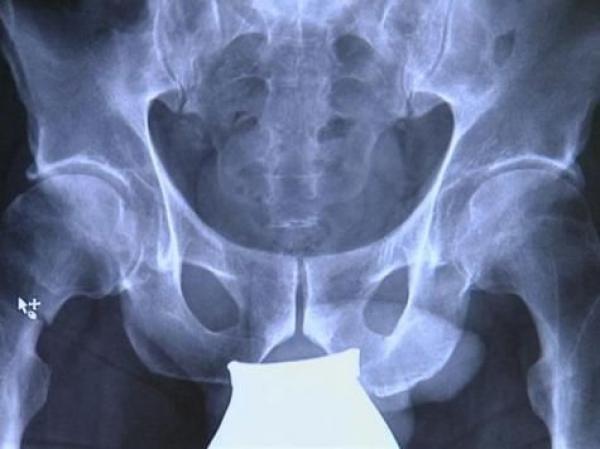

يعتبر كسر عنق أو مفصل الفخذ من الكسور الخطيرة للغاية. وتعالج هذه الكسور مؤخرا في ألمانيا بعمليات دقيقة باستخدام حوض اصطناعي، إلا أن فترة ما بعد العملية طويلة نسبيا وخطيرة، إذ تنتج عنها التهابات وآلام مزمنة.

وفي ألمانيا، يتم علاج كسر عنق الفخذ إما بتثبيت عنق الفخذ بواسطة مسامير أو بإجراء عملية جراحية يتم فيها زراعة عظم فخذ اصطناعي كامل. وبعد إجراء العملية يتوجب على المريض الخضوع لعملية إعادة تأهيل، وهي فترة طويلة وخطيرة، إذ من الممكن أن يتعرض الشخص للإصابة بالتهاب في الرئة لعدم قدرة الدم على الحركة بشكل طبيعي في الرئة بسبب الاستلقاء لفترة طويلة، مما يؤدي إلى صعوبة في التنفس، وفق هوفمان.